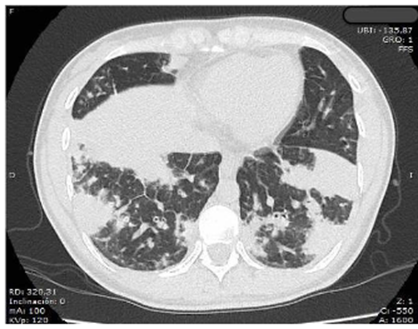

Se contaba con radiografía de tórax tomada en otra institución en la que se documentaron extensas opacidades parenquimatosas mixtas y ocupación alveolar, involucrando predominantemente los lóbulos inferiores, correspondiente a edema pulmonar evolutivo de origen no cardiogénico. Se decidió tomar tomografía computarizada de tórax de alta resolución (TCAR) (figura 1), cuyos hallazgos anormales se reportaron como consolidaciones bibasales confluentes y en lóbulo medio por probable neumonía multilobar y consolidaciones en lóbulos superiores; no se identificaron masas pulmonares ni derrame pleural, lo cual era concordante con la impresión diagnóstica inicial de neumonía.